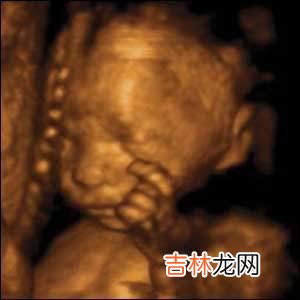

近来,在美国等地兴起了用超声波扫描器给腹中胎儿拍写真集的热潮 。美国全国各大购物中心都冒出了一些名为“胎儿摄影”、“产前拍摄”和“看看子宫”的连锁工作室,为准父母提前看到可爱宝宝提供服务 。

据6月14日出版的美国《人物》杂志报道,在美国为胎儿拍写真的收费在50美元-300美元之间,拍出的胎儿照片非常清晰,能够看到胎儿的表情,还能数清胎儿的手指和脚趾 。